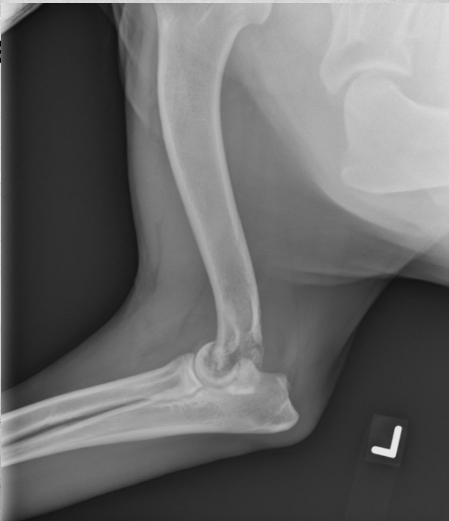

5

Q

8 months old female German Shepherd

Painful elbows

A

Both elbows: the anconeal process is ununited, the margins of the anconeal process and olecranon are markedly irregular and periosteal proliferation is present.

Marked intramedullary sclerosis of the olecranon and subtrochlear region of the proximal ulna is visible.

Diagnosis: Ununited anconeal process (UAP) and panosteitis of the ulnas.